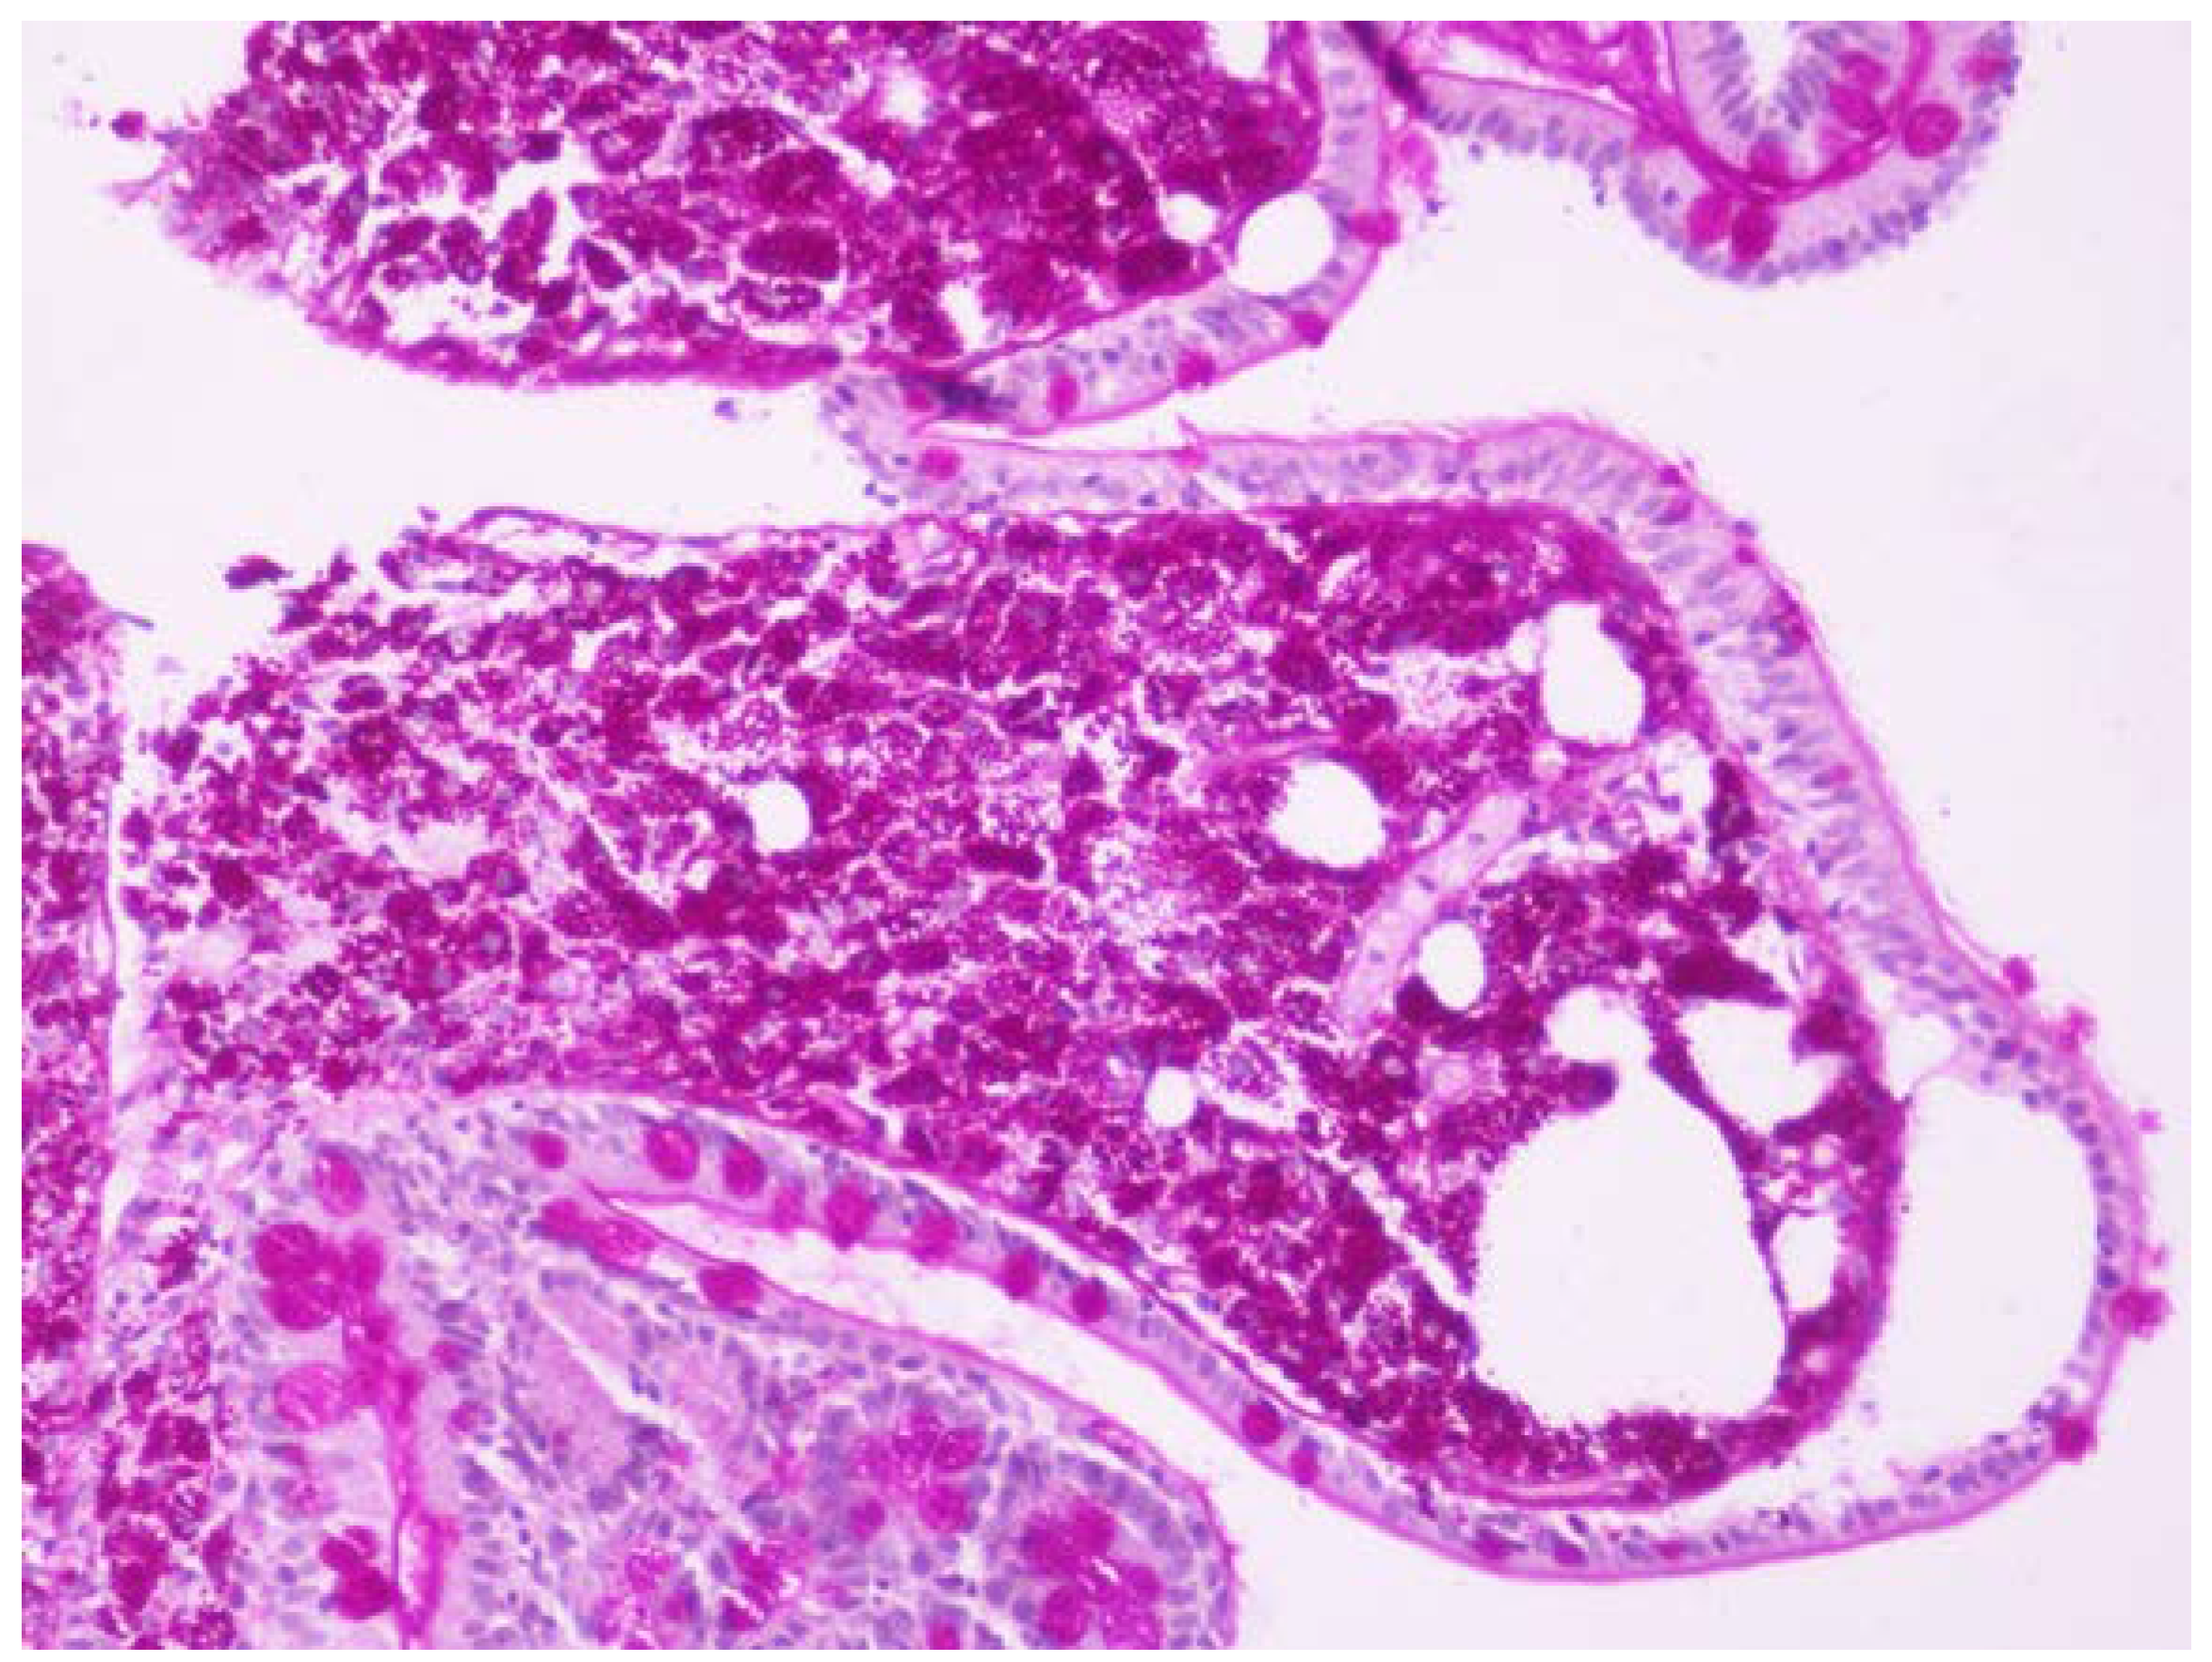

One month before admission the patient was referred to our endoscopy department due to chronic diarrhea and weight loss as an outpatient and she underwent gastroscopy with 2nd portion of the duodenum biopsies. One week before admission she was seen by her physician in the local hospital for low grade fever, weight loss and chronic diarrhea and she was referred to this hospital. Based on the initial history and findings a malabsorption syndrome was suspected. The slides were stained with hematoxylin and eosin (HE) and PAS and the biopsies revealed flattened villi, dense infiltrate of foamy macrophages with frequent PAS-positive bacilli within them, so Whipple’s disease diagnosis was suspected (Figure 1 and Figure 2).

Figure 2. Biopsy from the 2nd portion of the duodenum in magnitude. The same biopsy stained with hematoxylin and eosin (HE) and periodic acid–Schiff (PAS) showing a flattened villus in magnitude with a dense infiltrate of foamy macrophages.